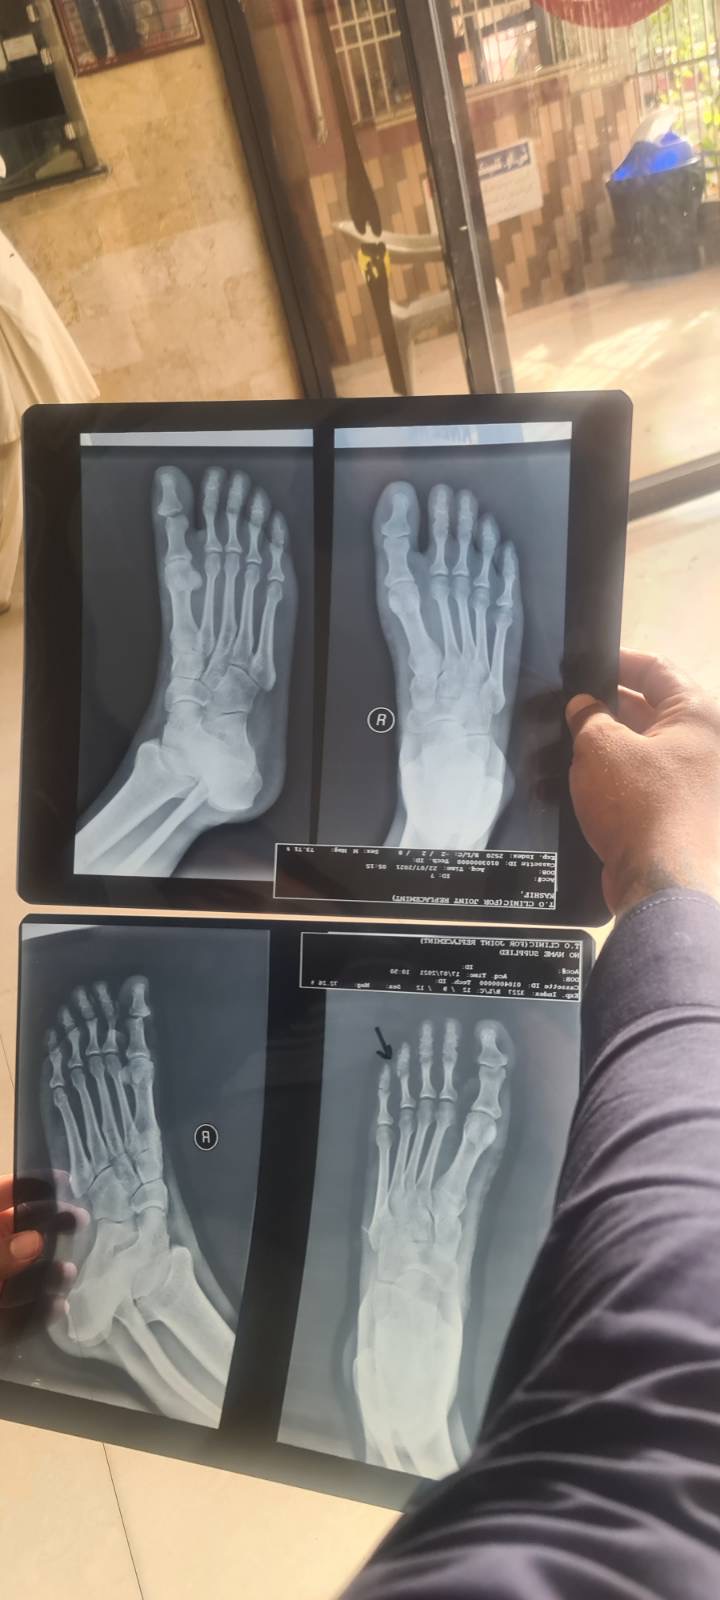

I had a fracture in my right foot thumb and i consulted a doctor they tried to set the bone and then advised me to place the foot kn cold water, then a week later om yesterday i went to have my xray done again and there is no change. Pain is still the same. And the bone i see in the xray is also same. Doctors said that the tissies are damaged and once the swelling is over the bone will be on its place. Please advise if this is gonne be okay on its own or should i get the bone fixed again Above xray is latest and below xray is a week before

This is actually not clear to see in x-rays. However, as per your indicator, it seems to fracture of middle phalanx of the 4th toe. it is usually treated with buddy strapping/immobilization. It takes about 2-3 weeks to relieve swelling. Don't put it into cold water but do icing or cold therapy and take simple painkillers to ease your pain. It will heal. Inshallah. Get consult with your same doctor again in 2 weeks if the problem doesn't resolve.